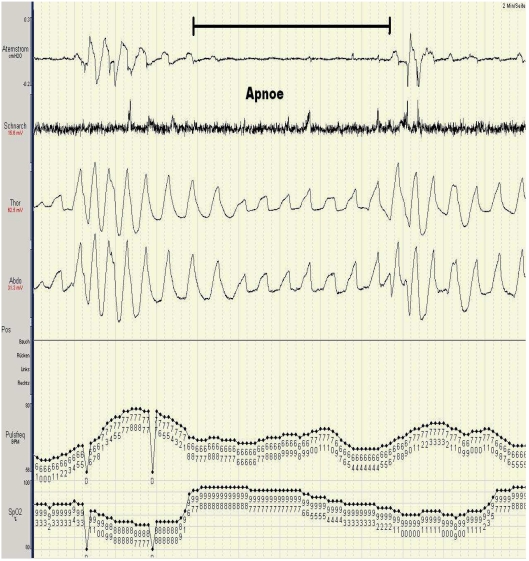

Obstructive sleep apnea (OSA) being the most frequent sleep related breathing disorder results in non-restorative sleep, an increased cardiovascular morbidity and mortality as well as an elevated number of accidents. In Germany at least two million people have to be expected. If obstructive sleep apnea is diagnosed early enough then sleep may regain its restorative function, daytime performance may be improved and accident risk as well as cardiovascular risk may be normalised. This review critically evaluates anamnestic parameters, questionnaires, clinical findings and unattended recordings during sleep regarding their diagnostic accurracy in recognising OSA. There are numerous tools with insufficient results or too few data disqualifying them for screening for OSA. Promising preliminary results are published concerning neural network analysis of a high number of clinical parameters and non-linear analysis of oximetry itself or in combination with heart rate. Nasal pressure recordings can be used for risk estimation even without expertise in sleep medicine. More data is needed. Unattended portable monitoring used by qualified physicians is the gold standard procedure when screening methods for OSA are compared. It has a very high sensitivity and specificity well documented by several meta-analyses.